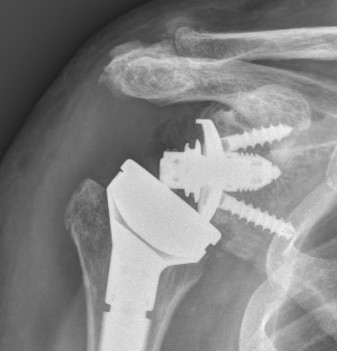

Reverse shoulder arthroplasty

Reverse

- socket in proximal humerus

- ball in glenoid

- center of rotation shifted medially and distally

- allows deltoid to apply compressive force and stabilize joint in absence of rotator cuff

Glenoid component

Metaglene / baseplate

Depuy Synthes Delta Xtend

Design

- uncemented

- coated central peg

- secured by compression non locking screws + locking screw

- +/- variable angle to allow inferior screws along scapular spine / superior screw into coracoid

Glenosphere

Press fit / morse taper onto baseplate

Lateralized / thicker options - limit scapular notching

Eccentric options - shift center of rotation inferior, limiting scapular notching